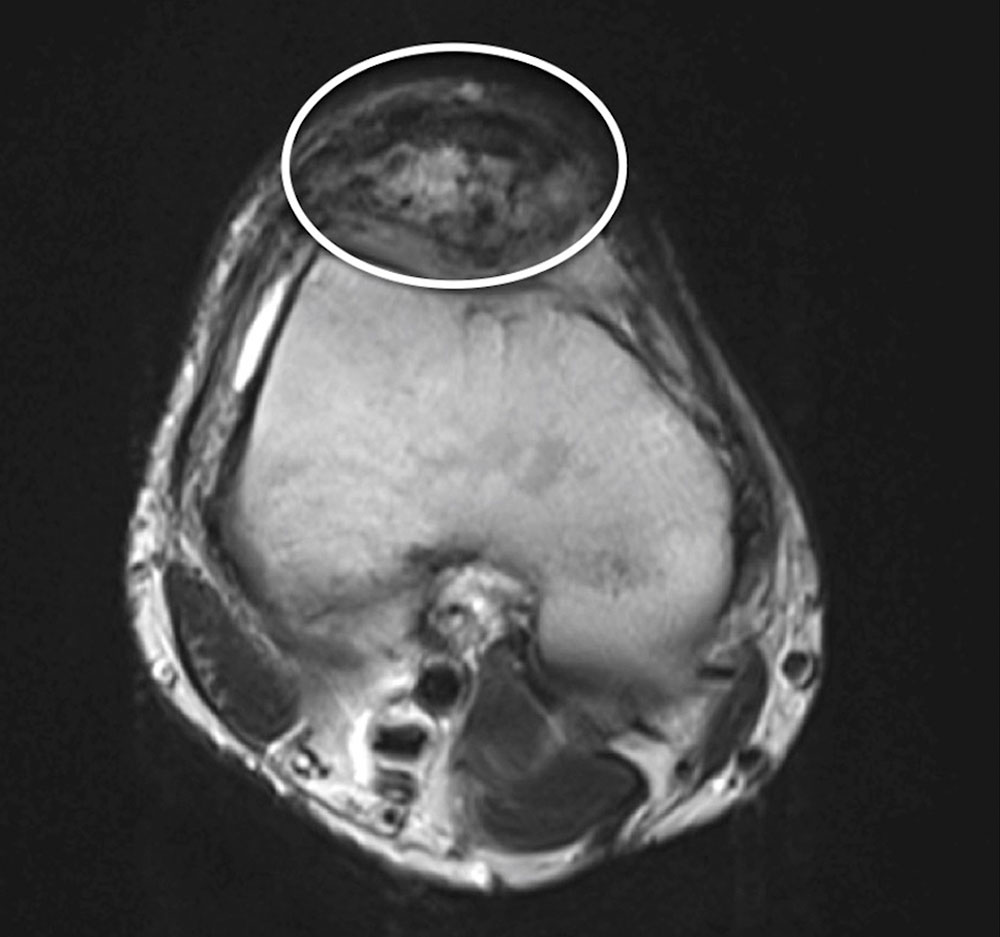

The imaging appearance is characterized by a large number of dilated inflow and outflow vessels, which extend into the surrounding tissue layers, usually without respecting classic anatomical borders. Imaging does not show an actual solid, circumscribed tissue lesion in the sense of a space-occupying mass, as often seen in vascular tumors. Rather, the absence of a defined solid mass is an imaging characteristic of an arteriovenous malformation (AVM). The nidus, as a net-like tangle of multiple small arteries and veins, presents as a localized proliferation of multiple, smaller vessels (“bag of worms”). Displacement of soft tissue that is characteristic of solid tumors is normally absent.

In addition, cross-sectional imaging using computed tomography (CT) or magnetic resonance imaging (MRI) is required to confirm the diagnosis, localization and involvement of organs. CT with contrast agent administration plays a lesser role in this context: it can easily detect bony involvement of the arteriovenous malformation, but spread to soft tissues is better visualized by MRI. The hemodynamics of the lesion can also be visualized by dynamic, contrast-enhanced MR angiography. In MRI, so-called flow voids are present in sequences without contrast medium because of the rapid blood flow. The dilated arteries supplying the nidus ("feeder arteries") usually follow a tortuous course. Depending on the angioarchitecture, single dominant dilated veins or several more net-like dilated veins can be delineated as the outflow of the lesion. The surrounding tissue may show edematous or fibrous-fatty changes. Involved bony structures may exhibit lytic changes or hyperplasia.